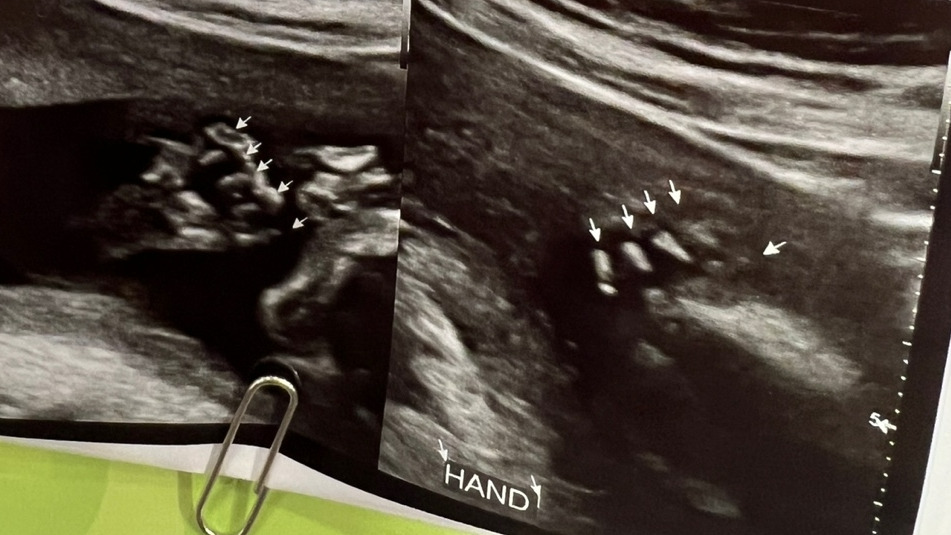

그리고 20주 차 3일에 드디어 하게 된 정밀초음파. 너무나도 오랜만에 보는 아기의 모습에 마음이 설렜고, 태동이 온전하게 느껴지지 않아 조금 시무룩하던 와중 초음파를 통해 본 아기의 모습이 너무나도 활동적이고 건강해서 마음이 많이 놓였다. (이 이후로 21주 차에 접어든 후 태동은 많이 느끼고 있다) 이제는 초음파 한 번에 온전히 들어오지 않는 아기. 20주 차에는 약 360g 정도였는데, 그 작은 몸에도 모든 장기와 손가락 5개, 발가락 5개에 필요한 것들은 다 지니고 있어 얼마나 신기하던지. 내 뱃속에서 저렇게 작지만 강인한 생명이 꼬물거리고 있단 생각에 나도 모르게 초음파를 보는 내내 눈물이 계속 났다. 남편은 20분 동안 초음파를 하며 누워있는 내 발가락을 지긋이 잡아주었다. 여하간 모든 검사가 "정상"이라는 이야기에 다시 한번 감사함을 느꼈다. 그리고 무엇보다 가장 걱정이 되었던 자궁경부 길이 (자궁경부 길이가 짧아지면 조산의 위험이 있다. 보통 2.5cm 이하부터 각별히 조심해야 한다.) 역시 5cm라는 말씀에 슬슬 운동도 시작하고, 출퇴근도 열심히 해야지!라고 생각을 했다.

내 차례를 기다리며 응급 침대에 누워있는데, 진통이 온 듯한 옆 산모의 신음소리는 정말 공포 그 자체였으며, 몇 달후 나의 모습일 것을 생각하니 갑자기 모든 것이 다 "현실적으로" 느껴졌다. 여하간 2-30분 정도 대기를 한 후 본 진료의 소견은 다행히도 양수는 아니지만, 자궁경부 길이가 2주라는 짧은 기간 동안 3.3cm로 줄어들어 긴 편은 아니라는 이야기를 들었다. 간단한 일상생활 정도는 가능하지만 가급적 눕눕을 권장, 재택으로 전환이라는 소견서 (인 줄 알았는데 진단서를 끊어주심...)를 받고 나는 그 이후로 일주일째 재택근무를 하고 있다.